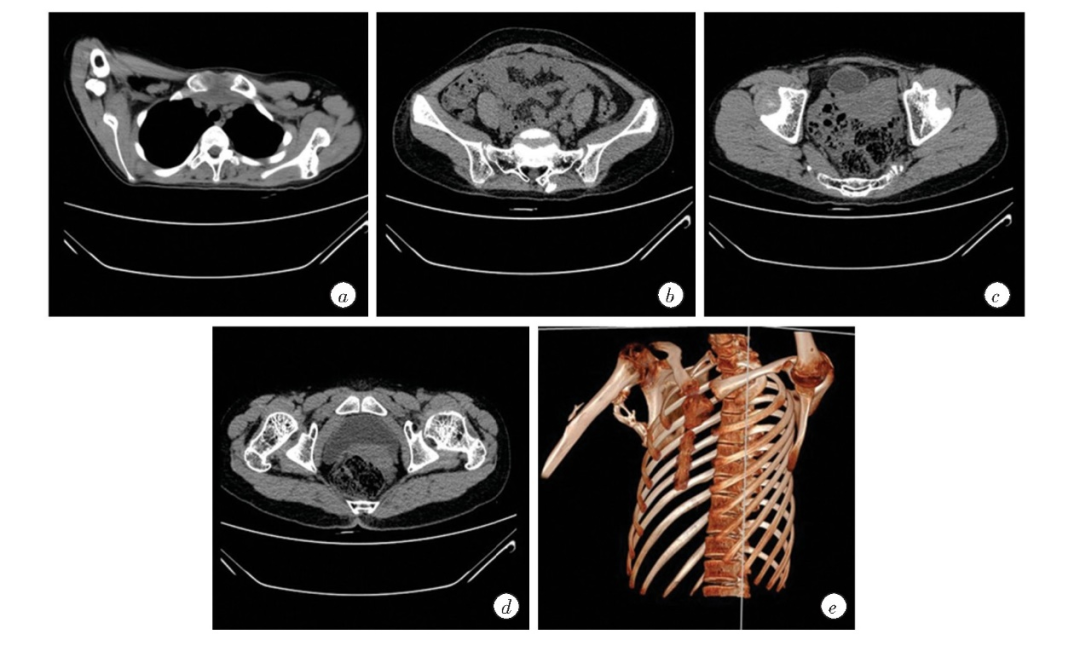

图3 患者胸部及全腹CT平扫、肋骨及肱骨CT三维重建(图源自文献)

a.胸部CT示右侧肱骨后方-肩胛骨的异位骨化;b.腹部CT示S1-2骶椎左后方异位骨化;c.腹部CT示耻骨骨软骨瘤;d.腹部CT示股骨颈骨软骨瘤;e.骨CT三维重建示右肩上臂及腋窝异位骨化